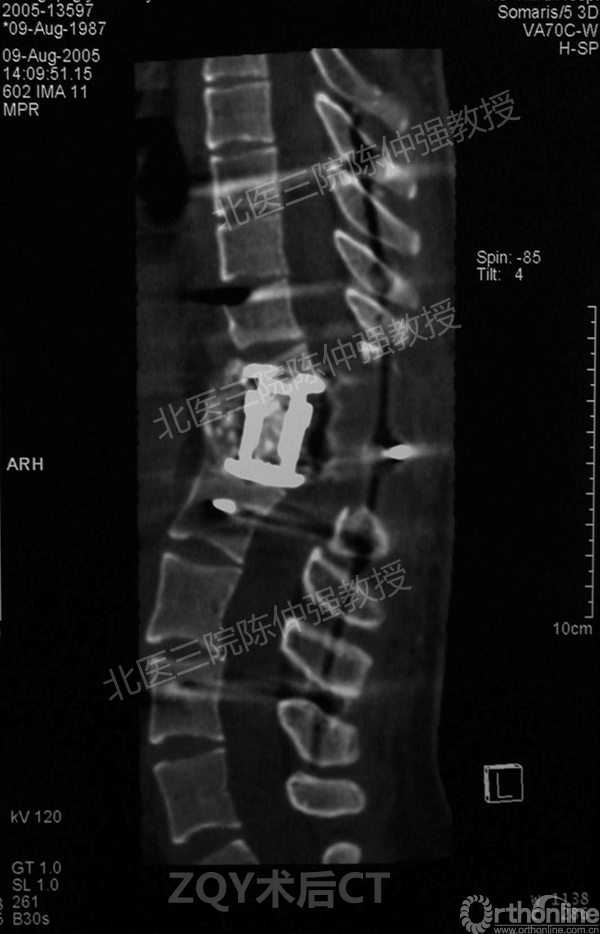

ZQY术后

患者女性17岁,胸腰椎陈旧结核性侧后凸畸形,局部呈“麻花状”扭转,无神经功能受损表现。2005年,陈仲强教授带领团队实施后路+侧前方联合入路脊柱节段切除、双轴旋转矫形术。术后患者外观显著改善,神经功能正常。术后随访证实患者截骨矫形节段骨性融合良好,矫形效果持续良好。